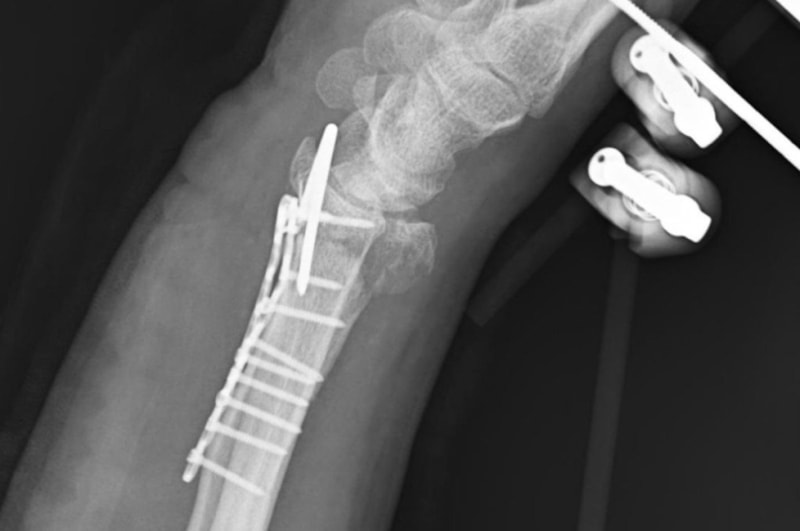

Sağ kolunda bilek kısmında parçalı kırık oluşan Arslantaş, ameliyat edilip, tedavisi tamamlandıktan sonra taburcu edildi.

Doktorlar, bilekteki kemiğin parçalı kırık olması nedeniyle tam iyileşmenin zor olduğunu belirtti. Yanı sıra his ve hareket kaybı yaşanabileceği ifade ettiler. Yaklaşık 3-3,5 saat süren ameliyatın ardından 2 ay kadar fizik tedavi görmem gerektiği söylendi.